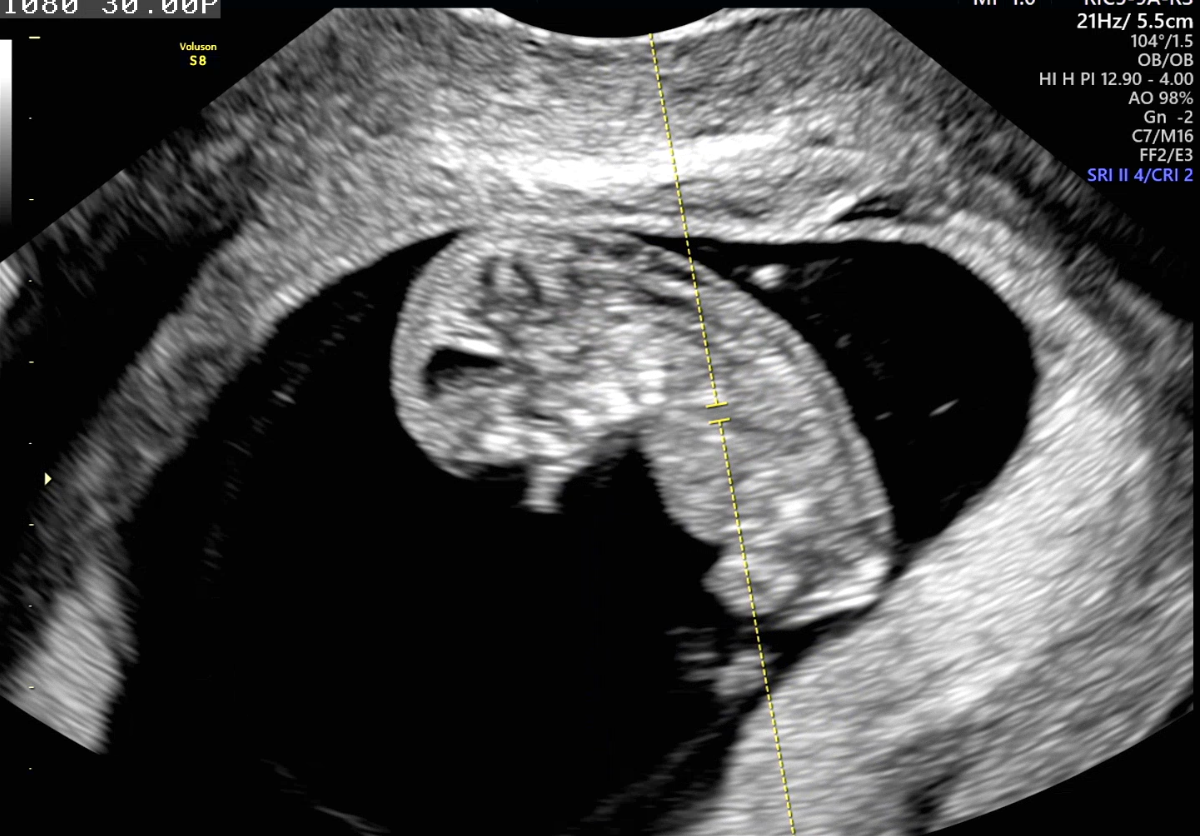

| 가슴 떨리는 임신 이야기를 공유해 주세요. | 처음에는 ‘하면 되겠지’라는 긍정적인 마음으로 시작했지만, PGT 검사 통과 실패와 5일 배아까지 도달하지 못하는 상황이 반복되며 6개월 가까이 이식조차 한 번도 하지 못했습니다. 여러 번의 실패 끝에 아직 포기하기는 이르다고 생각해 다시 도전했고, 네 번째 시험관 시도에서 임신에 성공할 수 있었습니다. |

| 치료 도중 느꼈던 가장 기뻤던 순간과 절망적인 것들은 무엇인가요? 잊지 못할 경험이 있나요? | 시험관 4차 만에 피검사 1차를 통과했던 날이 가장 기뻤습니다. 대학 합격 발표를 확인할 때보다 더 떨렸던 순간이었습니다. 반면 시험관 3차까지 진행하고도 이식 한 번 하지 못한 채, 보유한 배아가 단 하나도 없다는 사실을 알았을 때는 가장 절망적이었습니다. |